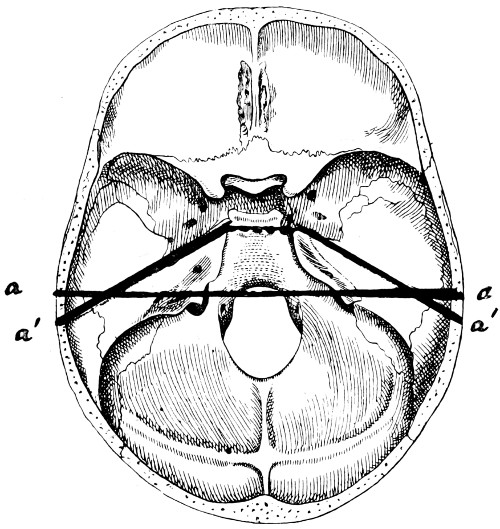

28. Illustrating the lines along which forces received on the vault are transmitted to the base 69

30. Plan of the base of the skull 77

31. To illustrate the relation of basic fractures to cranial nerves 81

32-37. The lines pursued by basic fractures 83-8

38 A and B. To illustrate the probable source of profuse hæmorrhage from the ear 97

39. To show the relation of a typical basic fracture to the middle ear and its adjuncts 103

40 and 41. To show the relation of basic fractures to the petrous bone 104, 105